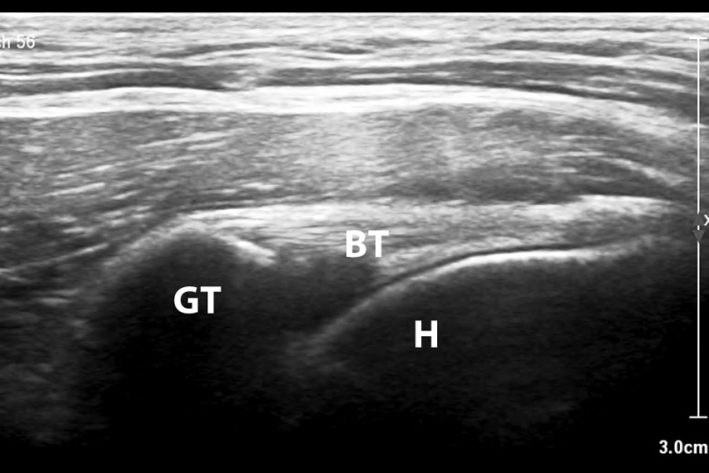

Die klinische Untersuchung liefert einen ersten Hinweis auf eine Schultergelenkserkrankung. Zur weiteren genauen Diagnosestellung wird meist eine Kombination aus Ultraschall und CT durchgeführt. Eine Entzündung und auch eine Teilruptur wird hier in den meisten Fällen erkannt. Bei einer Luxation kann die Diagnosestellung schwieriger sein, da sich die Sehne nicht immer in der luxierten Position befinden. Der Goldstandard zur Diagnostik ist in unklaren Fälle die Arthroskopie des Schultergelenkes.